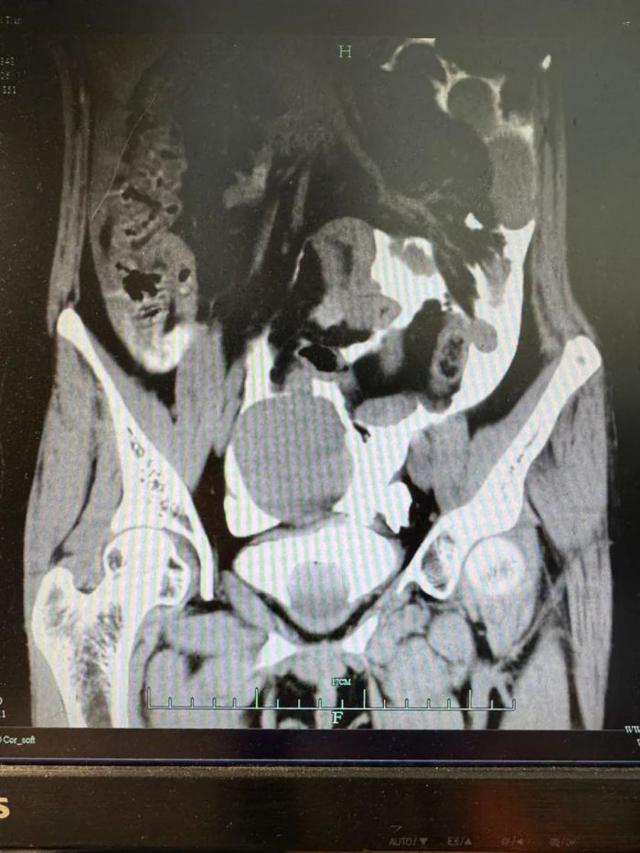

经超声和CT检查显示,小李的腹腔内有大量的液体,腹腔穿刺吸出淡红色血性液体。

患者CT影像

“立刻安排膀胱造影!病人很可能膀胱破了!”泌尿外科秦勇主任紧急会诊后,认为病人虽无明显腹部外伤痕迹,但根据病史描述及症状表现判断膀胱破裂可能性较大。随后的CT膀胱造影检查结果证实了秦主任的判断,同时也让所有人倒吸冷气:膀胱真的破了,腹腔里积存了十几个小时的尿液!